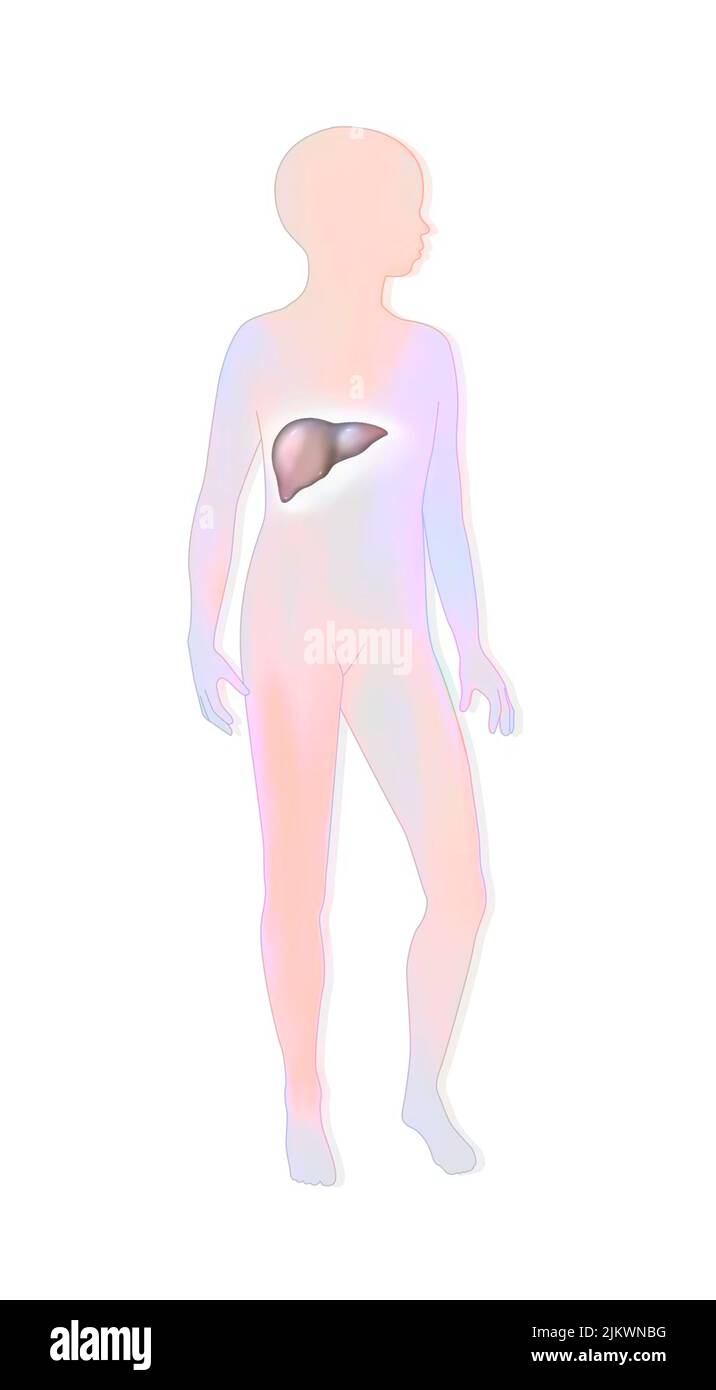

(4,132)Page 1 sur 42

Résultats de la recherche pour les photos et les images (4,132)

Page 1 sur 42